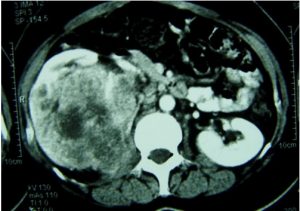

![]() 중국과학원 베이징게놈연구소 류장(劉江) 연구팀이 시카고대학과 공동으로, 저(低)산소 생리조건에서 SPOP 핵단백질(nucleoprotein)의 과도발현과 세포 내 잘못된 위치가 신장암을 유발하는 핵심 요소임을 규명하였다. 관련된 연구논문은 최근《Cancer Cell》지에 온라인으로 게재되었다. 신장암은 비뇨생식계통에서 자주 발생하는 악성 종양으로서, 성인의 악성 종양 중 3%를 차지한다. 주요한 치료법은 근치성의 신장 제거술인데, 신장암은 조기 임상증세가 뚜렷하지 않아서 30% 정도의 환자가 확진 시 이미 전이가 발생한 상태이다. 게다가 방사성 치료와 화학성 치료의 효과도 좋지 않다. 따라서 현재 신장암의 발병메커니즘을 규명해 조기진단과 치료에 필요한 분자타깃을 찾아내려는 연구가 경쟁분야를 형성하고 있다. 투명세포암(clear cell carcinoma)은 신장암의 가장 흔한 유형으로서 전체의 75%를 차지한다. SPOP은 E3 유비퀴틴 접합효소(ubiquitin ligase)의 일종인 Cul3과 기질(substrate)을 연결시키는 교량 단백질로서, 핵단백질의 유비퀴틴화를 유도하는 방식으로 세포 제어에 참여한다. 류장(劉江) 연구팀은 SPOP 핵단백질이 99%의 신장 투명세포암 조직에서 과도 발현되지만, 대응하는 정상적인 신장조직에서는 발현수준이 매우 낮음을 발견하였다. 또한 전이성의 신장 투명세포암에서도 SPOP 핵단백질이 과도발현됨을 발견하였는데, 이는 SPOP가 투명세포암의 마커분자임을 뜻한다. 심층적인 연구결과, 저산소 환경이 신장암 조직에 과도발현된 SPOP 핵단백질로 하여금 세포질 속에 대량으로 축적되도록 하였다. 세포핵 속에 축적되는 SPOP는 세포의 자멸을 제어하지만, 세포질 속에 축적되는 SPOP는 세포의 증식을 가속화할 수 있다. 신장암조직의 SPOP 핵단백질은 세포증식을 통해 종양을 생성시킨다. 연구자들이 SPOP 핵단백질을 제거했더니 신장암세포가 사살되었고, 정상적인 세포는 큰 영향을 받지 않았다. 이 연구는 신장암 속 SPOP 핵단백질의 원 발암유전자(proto-oncogene) 기능을 규명하고, 신장암의 진단과 치료를 위해 잠재적인 분자타깃을 발견했다는데 의미가 크다고 전문가들이 평가하였다. 정보출처 : http://news.sciencenet.cn/sbhtmlnews/2014/3/285039.shtm |